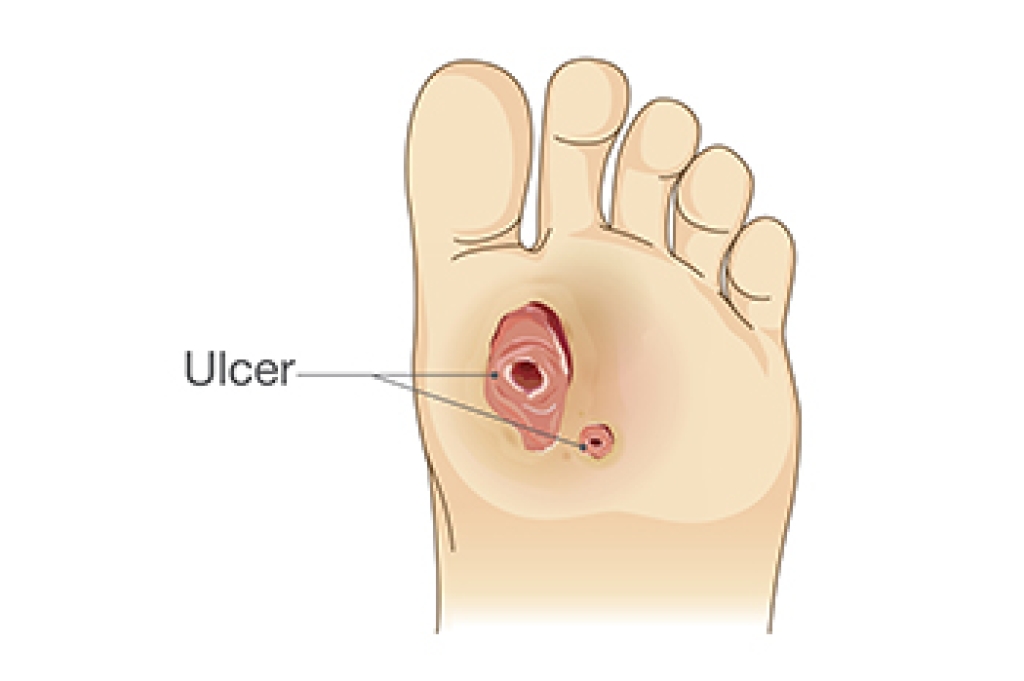

Causes of Foot Ulcers in Diabetic Patients

One of the most concerning complications of diabetes is the development of diabetic foot ulcers. A primary culprit behind diabetic foot ulcers is peripheral neuropathy, a condition where nerve damage impairs the ability to feel sensations in your feet. Without pain awareness, you may not notice the pressure your feet experience during everyday activities. This can lead to developing blisters, lesions, or sores. If these injuries are not attended to, they may evolve into foot ulcers. Another significant factor in the development of diabetic foot ulcers is poor blood flow, which can happen as a result of conditions such as peripheral arterial disease. Inadequate blood supply can hinder proper wound healing, making minor injuries prone to infections. Diabetic foot ulcers are a serious concern, and understanding the causes, in addition to taking preventive measures, can significantly reduce the risk. If you have diabetes, it is strongly suggested that you schedule regular check ups with a podiatrist who can both monitor and treat any foot problems as they arise.